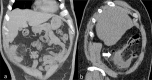

Diverticular disease is a common disorder and its incidence increases with ageing. Pathophysiology is multifactorial. Lifestyle, including smoking, alcohol intake, decreased dietary fibres and lack of physical activity, plays a predominant role. Genetics seems also to contribute specifically for right-sided diverticular disease (RSD). The majority of the patients with diverticular disease are asymptomatic. Diverticulitis is the inflammation of the diverticula usually presenting with abdominal pain associated to nausea, vomiting, rectal bleeding, diarrhoea and fever. When the inflammation process affects the diverticula in the ascending colon, the condition represents a clinical challenge as it can be easily misdiagnosed with other acute abdominal emergencies. We reported a case of a 70-year-old female who presented to our Emergency Department (ED) with right upper quadrant pain and an initial clinical suspicion of cholecystitis. Ultrasound (US) and Computed Tomography (CT) demonstrated an anatomical variation of the sigmoid colon diverticulitis. This clinical report demonstrates that ultrasound plays a relevant part as first-step approach to the acute abdominal conditions and its accuracy increases together with other diagnostic tools such as Computer Tomography.